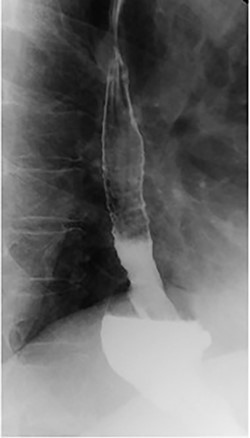

She underwent an upper gastrointestinal series that showed a normal-appearing stomach without any evidence of her prior gastroplasty, moderately sized hiatal hernia and slight delay in passage of contrast through the gastroesophageal junction (Fig. 1). On subsequent endoscopy, she was noted to have multiple loosely placed sutures within the gastric lumen along the greater curvature (Fig. 2), as well as a large-sized paraesophageal hernia.

Barium swallow showing hiatal hernia postendoscopic gastroplasty.